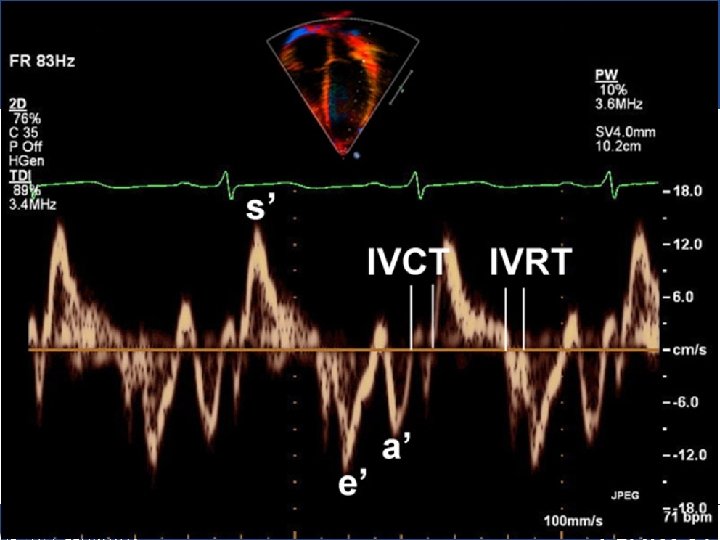

Radiology • Ultrasound – Doppler echocardiography is a noninvasive technique for determining: § the blood flow velocity in different locations in the heart. § the uterine artery blood flow velocity during pregnancy, as well as the fetal heart rate. Medical Terminology for Health Care Professionals, 8 e Jane Rice Copyright © 2015 by Pearson Education, Inc. All Rights Reserved